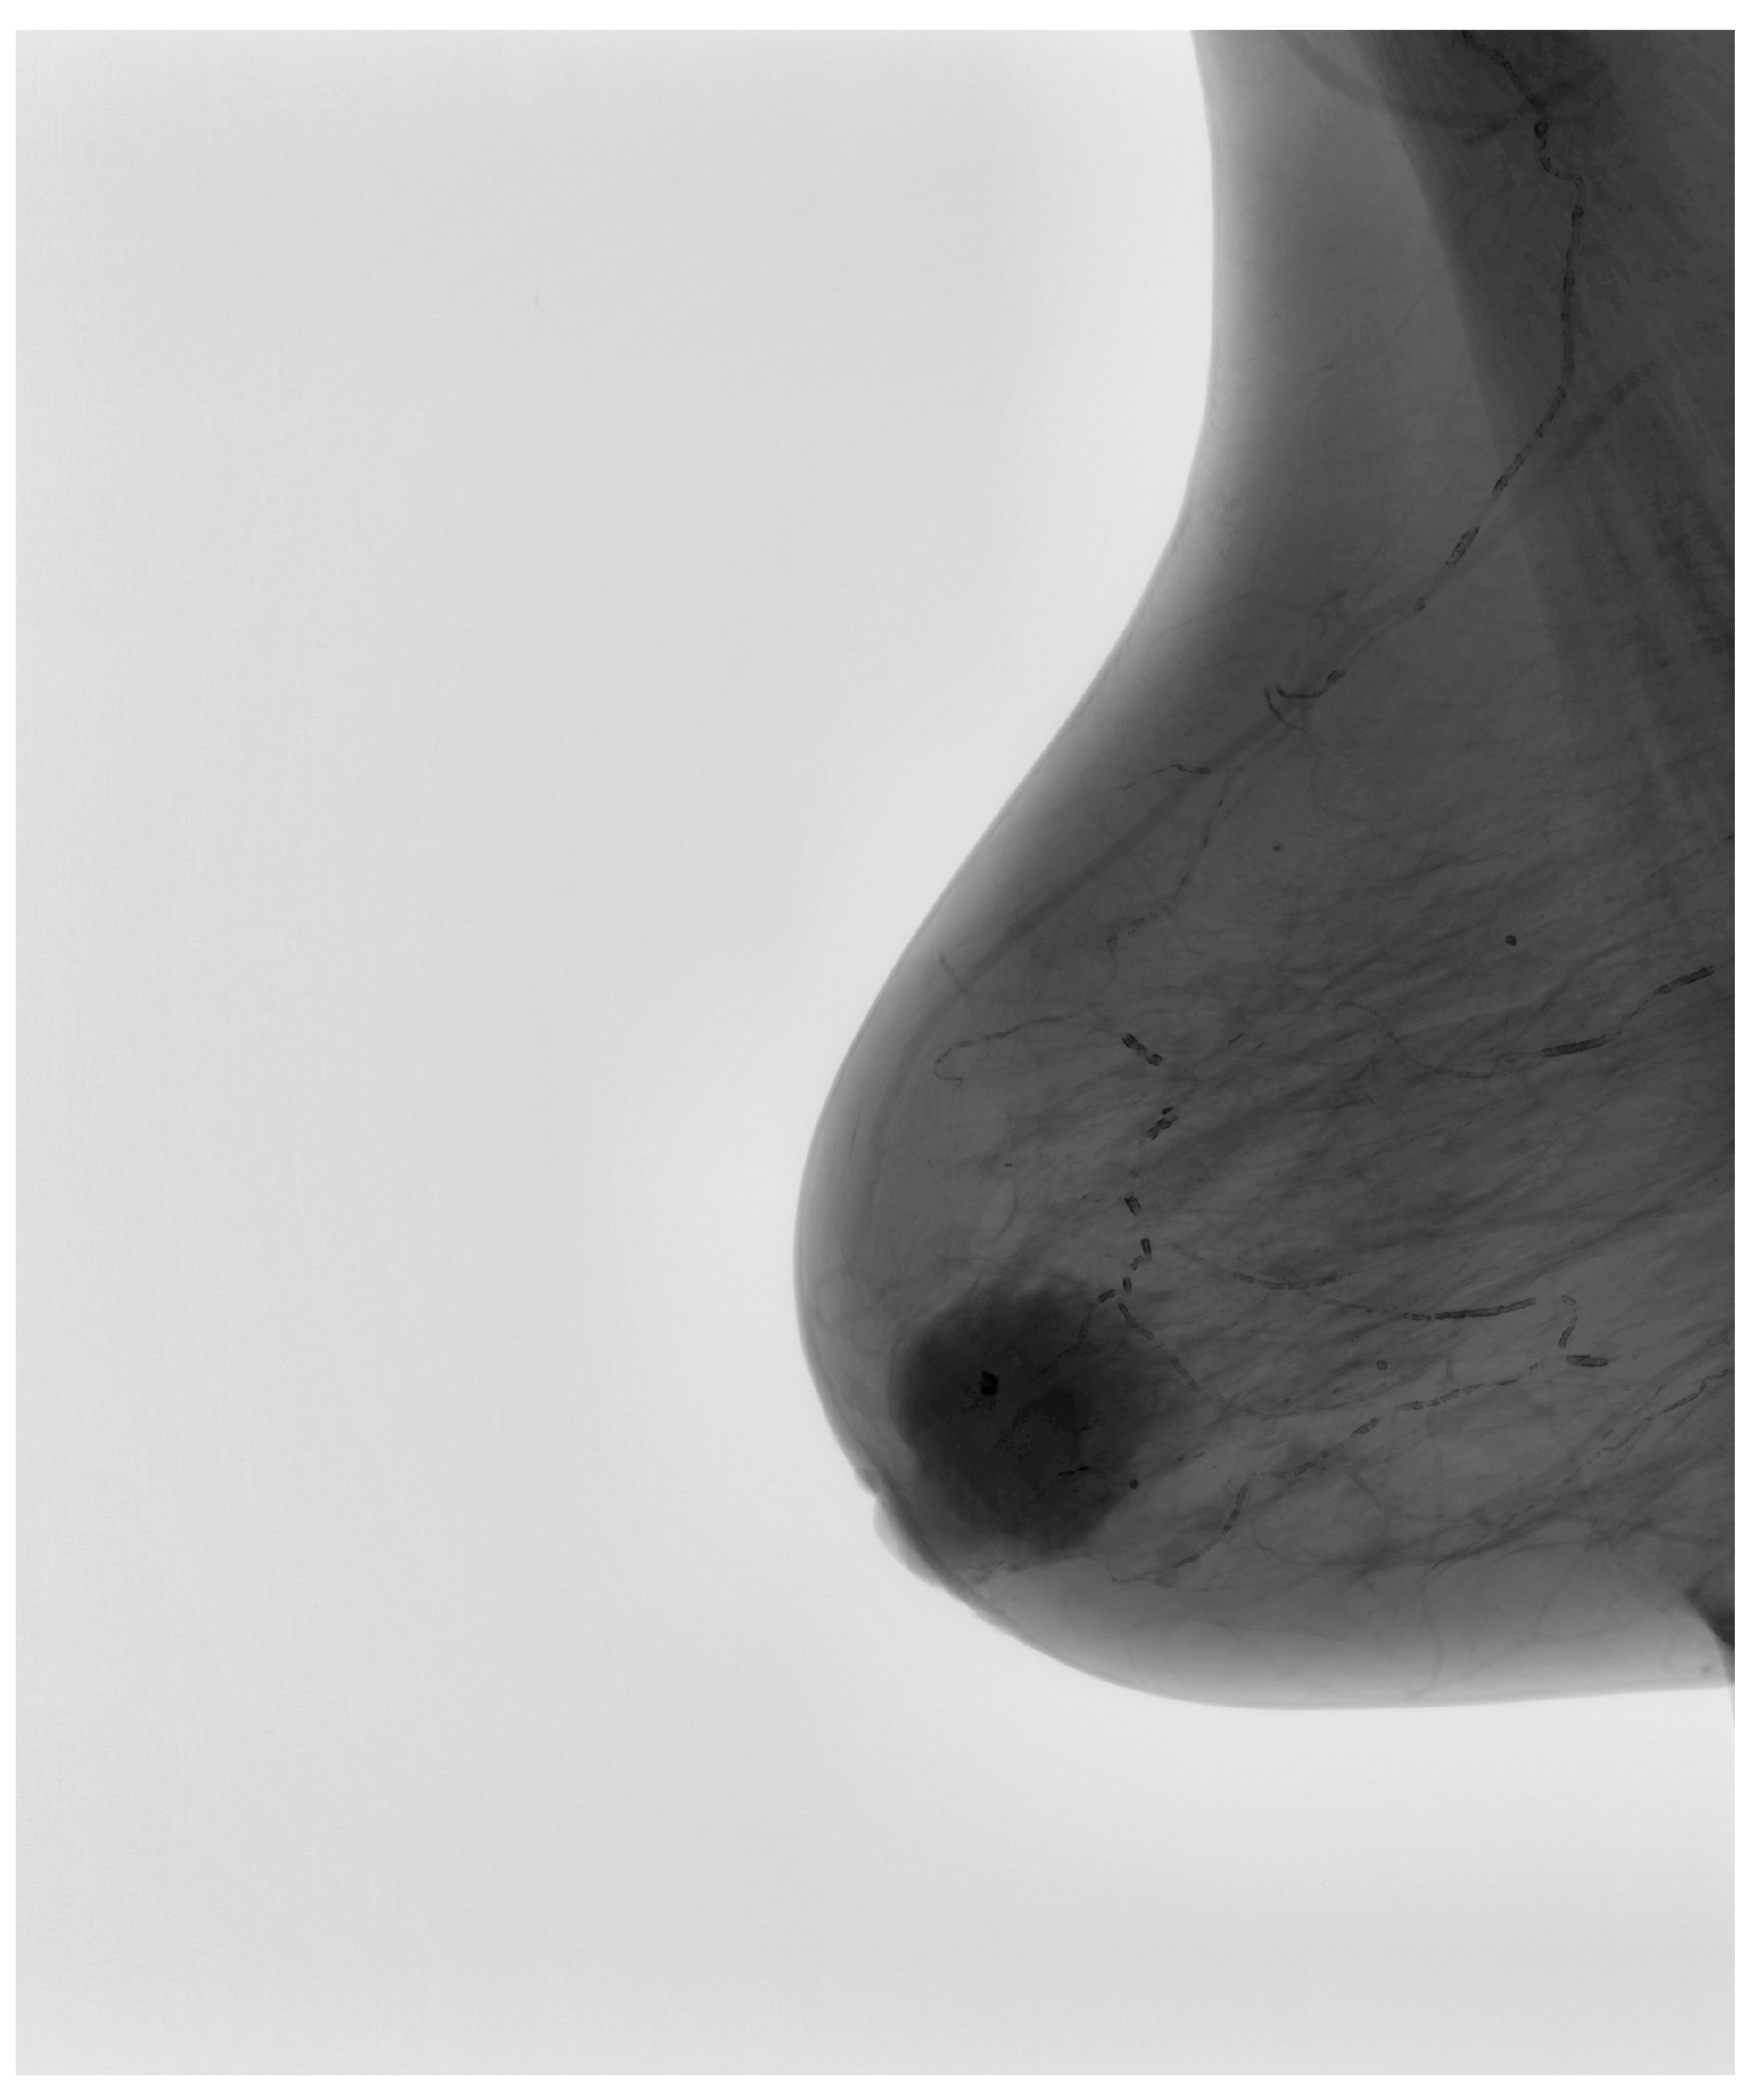

The preprocessing of mammographic images plays a fundamental role in ensuring the effectiveness of AI-based classification. To create a dataset suitable for deep learning, images originally acquired in the Digital Imaging and Communications in Medicine (DICOM) format were converted into the Portable Network Graphics (PNG) format. This step ensured compatibility with modern deep learning frameworks while maintaining structural fidelity and preserving critical radiological details. Figure 2 illustrates this transformation, highlighting how the conversion process retains fine-scale features essential for lesion detection.

Figure 2.

Example of DICOM to PNG conversion, demonstrating the preservation of essential mammographic structures.